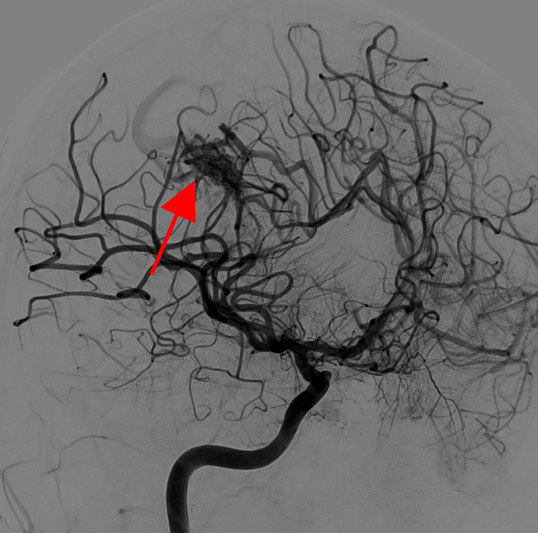

Giulio (nome di fantasia) è un ragazzo di quindici anni che viene condotto in Pronto Soccorso (PS), trasferito da un presidio riabilitativo territoriale, per dolore inguino-scrotale. La sua anamnesi è silente fino al mese prima, quando, in pieno benessere, ha presentato cefalea acuta, vomito a getto e perdita di coscienza. La TC encefalo ha documentato la presenza di un ematoma intracranico parietale destro atipico e l’angiografia ha dimostrato una malformazione artero-venosa (MAV) (Figure 1-3).